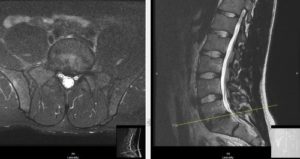

Позвоночная грыжа классифицируется зависимо от локализации, размеров, течения патологии, анатомического расположения. МРТ диагностика позволяет одновременно выявить отношение грыжи к каждому классу.

Грыжа отчетливо видна при МРТ-исследовании

- магнитно-резонансная томография;